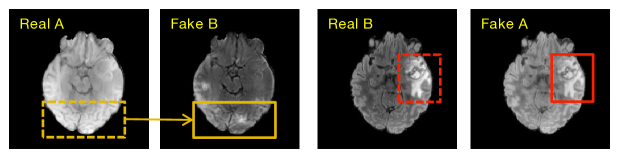

Look back cross-modality neuroimage synthesis. From the evolution standpoint, natural image-to-image translation leads the development of cross-modality neuroimage synthesis. Inspired by dictionary learning (Aharon et al., 2006), Roy et al. (Roy et al., 2013) trained two dictionaries where the input image is used to find similar patches in a source modality dictionary and the corresponding target modality counterpart will be extracted from the target dictionary to generate the desirable modality data. The work of Huang et al. (Huang et al., 2016) improves the quality of cross-modality synthesis by imposing a graph Laplacian constraint in a joint dictionary learning framework. Wang et al. (Wang et al., 2017) synthesizes the missing DT images from T1-w scans by learning a region-enhanced joint dictionary. When pix2pix (Isola et al., 2017) was released in 2017, the situation drastically changed. Most supervised cross-modality neuroimage synthesis algorithms adopt variants of pix2pix. Maspero et al. (Maspero et al., 2018) directly employ pix2pix to synthesize CT scans from MRI. The work of Olut et al. (Olut et al., 2018) synthesizes magnetic resonance angiography (MRA) from T1 and T2 with the addition of a steerable filter loss on pix2pix. Furthermore, CycleGAN (Zhu et al., 2017) boosts the performance of unsupervised cross-modality neuroimage synthesis. Hiasa et al. (Hiasa et al., 2018) employ gradient consistency loss to optimize the edge map of the synthesized neuroimage. Zhang et al. (Zhang et al., 2018b) propose two segmentation networks to segment the corresponding image modality into semantic labels and provide implicit shape constraints on the anatomy during translation. Chen et al. (Chen et al., 2018) propose a similar method to the work of Zhang et al. (Zhang et al., 2018b). The only difference between them is that the segmentation network of Chen et al. (Chen et al., 2018) is trained offline and fixed during the training phase of the image translation network. The inherent properties of medical images are ignored even though natural image-to-image translation approaches reveal many insights into cross-modality neuroimage synthesis. For instance, Fig. 3 shows a failed case of CycleGAN (Zhu et al., 2017) for cross-modality neuroimage synthesis. In particular, the lesion region of the target modality (red box of Fake A) cannot be accurately synthesized in comparison to the lesion region of the source modality (red dashed box of Real B), particularly for the structural details. Therefore, it is necessary to investigate more deeply to characterize the network architecture for the imaging principle of neuroimages.

Figure 3. A failed case in multi-modality brain image synthesis. In addition to generating low-resolution images, another problem is that the disease-related regions cannot be synthesized well. For example, when the target modality (Fake B) is generated from the input real modality (Real A), there exist failed regions (box) that are learned from the original ones (dashed box).